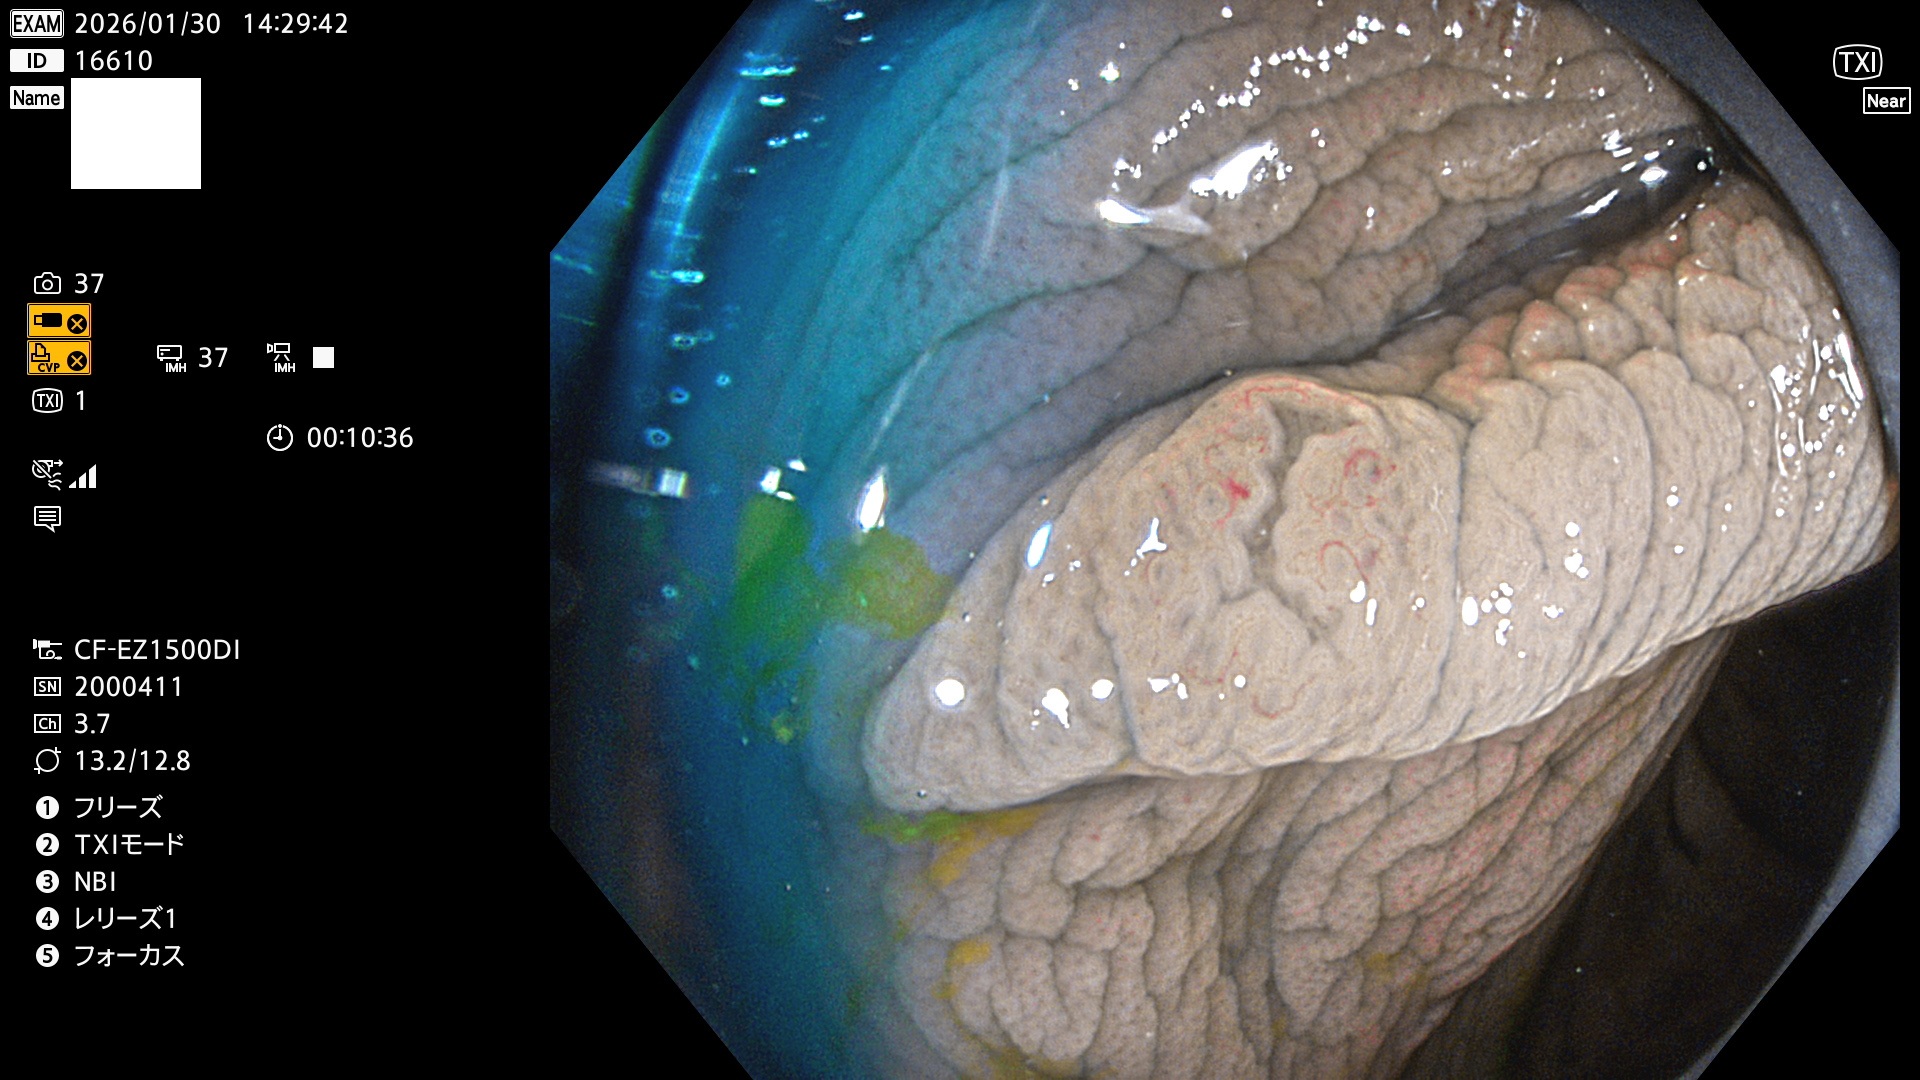

完全に平坦な物をUb、陥凹している物をUcと呼びます。Ubは認識が困難で、Ucはびらん(炎症)と紛らわしいために見落とされやすく、「内視鏡後・大腸癌」の原因になります。

毎週の検査(木・金・土・日)に発見されたUbとUc型・腺腫を、その週の日曜の夜にUPし1週間、提示します。

2026年1月29日〜2月1日の4日間(40件)10個 (Uc_ADR=10個/40人=25%)